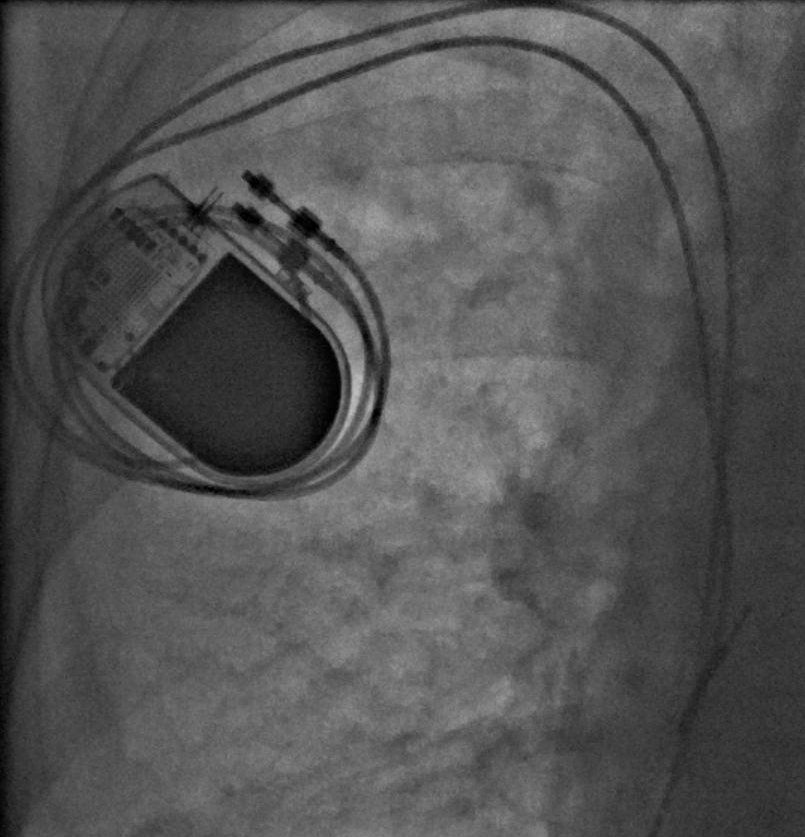

二、埋藏式永久心脏起搏:对于慢性心律失常、心衰等疾病,可以用各种各样的起搏器,模仿生理起搏,满足心脏病患者个性化治疗需求。